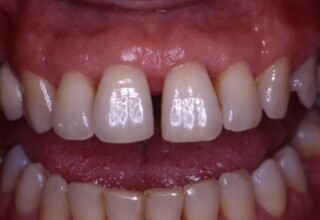

Restoration of bilateral diastemas between central and lateral incisors.

Diastemas were created mainly because of narrow laterals. After orthodontic treatment was finalized, the diastemas were closed with two composite resin restorations.